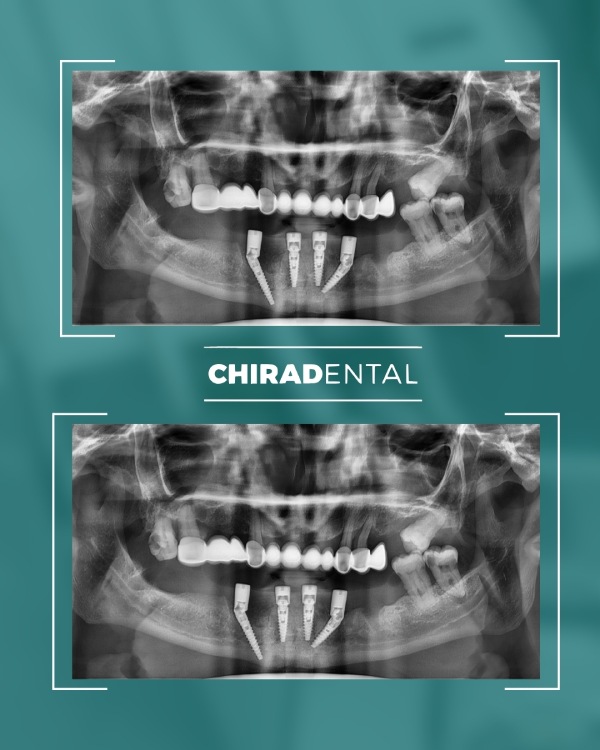

Ak tieto informacie nemáte, nevadí. Počas konzultácie vykonáme všetky potrebné vyšetrenia – rádiologické vyšetrenie ortopantomogram (skr. OPG) röntgenový snímok alebo 3D snímka CT (CBCT), odtlačky (3D sken) čeľustí, fotografovanie a videodokumentáciu chrupu, čeľustí, úsmevu, tváre a ďalšie diagnostické úkony. Na základe získaných údajov budete môcť absolvovať primárnu konzultáciu s naším špecialistom

Moderné technológie umožňujú rýchlo, spoľahlivo a esteticky obnoviť celú čeľusť, a to aj v zložitých prípadoch. Ponúkame niekoľko kompletných rehabilitačných systémov založených na počte implantátov a úrovni fixácie budúcej štruktúry. Možnosť 1 - All-on-4 (Základné riešenie) Táto metóda je vhodná pre pacientov so zníženým objemom kosti alebo pre tých, ktorí chcú nové zuby čo najrýchlejšie. Čo robíme: Inštalujeme 4 implantáty do hornej alebo dolnej čeľuste; V prípade potreby vykonáme augmentáciu kosti a plastiku ďasien počas tej istej návštevy; Nasledujúci deň odoberieme odtlačky pre dočasnú štruktúru; Po 3-5 pracovných dňoch pacient dostane dočasné kovovo-akrylátové zuby na dlhodobé nosenie. Výsledok: približne 10 nových zubov, ktoré umožňujú pohodlné žuvanie a úsmev. Po 3-6 mesiacoch vykonávame trvalé rekonštrukcie s použitím kovovo-keramiky alebo zirkónu. ⭐ Možnosť 2 — All-on-6 (štandardné riešenie) Optimálna možnosť pre pacientov, ktorí vyžadujú väčšiu stabilitu a väčšiu žuvaciu záťaž. Čo robíme: Inštalácia 6 implantátov so súčasnou augmentáciou kosti a ďasien; Odtlačky sa robia nasledujúci deň;Dočasné kovovo-akrylátové korunky sa inštalujú po 3-5 dňoch.

Výsledok: kompletný oblúk 14 zubov. Definitívna rekonštrukcia (kovovo-keramika alebo zirkón) sa vykonáva po 3-6 mesiacoch.